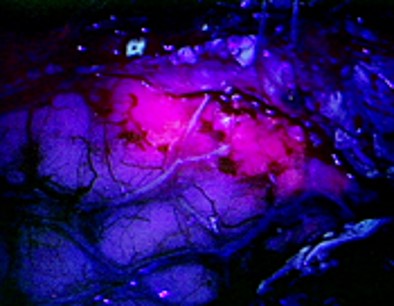

During surgery using Gleolan, the neurosurgeon views the brain through a special blue light filter on the surgical microscope.  Under this blue light, the active substance in Gleolan, aminolevulinic acid (ALA) is converted to a fluorescent compound that causes tumor cells to fluoresce a red-violet color while non-cancerous brain cells appear blue.  This procedure, known as fluorescence guided surgery, may allow the neurosurgeon to safely remove more of the tumor tissue.  Prior to Gleolan, this surgery would be performed under white light alone, making it difficult to differentiate malignant and non-malignant tissue.

Dr. Christian Ramsey of Baptist Health Lexington performed the first fluorescence-guided neurosurgery in the state last fall, using Gleolan in conjunction with blue light.  “It is great to be the first to have a technology that allows us to maximize more complete resections for these very challenging tumors,“ he says.